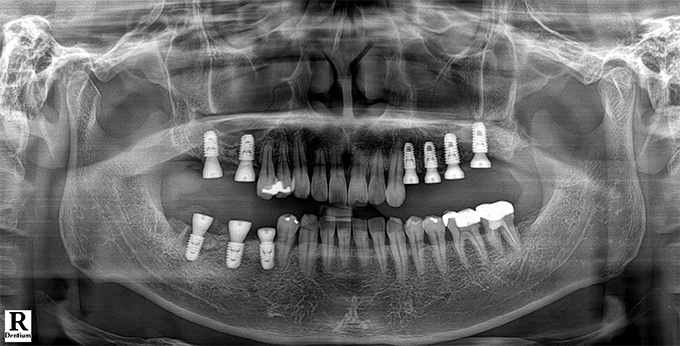

Before & After

임플란트 전후사진

before

2022.11.22

After

2022.12.09

※ 상기 치료전후 사진은 환자의 동의 하에 게재되는 것이며 동일한 촬영각도로 촬영 하였고 치료 기간을 명시하였습니다.

이러한 치료의 결과는 이 환자분에게만 해당되는 것이며 환자의 상태에 따라 똑같은 결과를 얻지 못할 수도 있습니다.

환자분의 상태에 따라 치료 기간, 효과 및 부작용은 상이할 수 있습니다.

치료전후 사진 게재는 의료법 제 23조, 제56조에 의거하여 게재합니다.